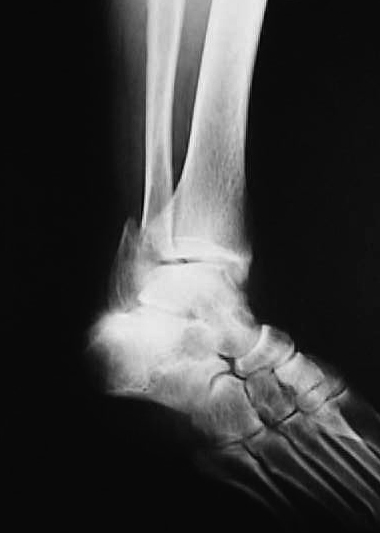

正面像において腓骨下端部の骨折が認められ、中枢骨片の内側への転位が認められた。側面像において中枢骨片は前下方、末梢骨片は外後上方の骨片への転位が認められた(図1、2)。

図1

図2